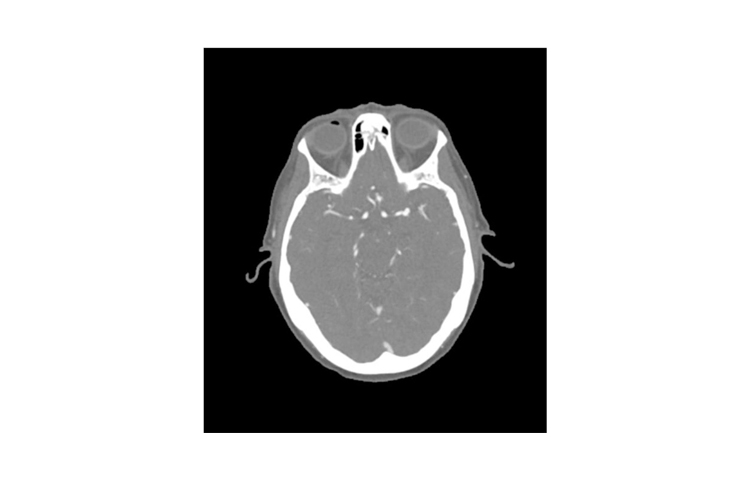

德國phantomx 50-03頭部CTA動脈瘤模體

德國phantomx 50-03頭部CTA動脈瘤模體模擬了在動脈期增強對比劑的頭部(CT 血管造影)。它從頂點到枕骨大孔。模體有三個顱內(nèi)動脈瘤,分別是中大腦動脈(MCA)、前交通動脈(ACoA)和基底動脈。

該模體可用于 CT(包括 CBCT)以評估和優(yōu)化成像性能及 AI 診斷。它也適用于培訓目的。模體提供了血管結構、軟組織和骨骼組織的詳細和逼真模擬,包括淋巴結等小細節(jié)。空氣空隙被約 -160 HU 的纖維素-聚合物復合材料填充。

德國phantomx 50-03頭部CTA動脈瘤模體規(guī)格

尺寸:約 191 x 218 x 150 毫米

重量:約2680克

基礎材料:纖維素-聚合物復合材料

最佳管電壓:120 千伏峰值 – 可根據(jù)要求進行調整 –

德國phantomx 50-03頭部CTA動脈瘤模體診斷特征

頭部血管、骨骼和軟組織的逼真模擬。

動脈瘤:

大腦中動脈 (MCA)

左側

前交通動脈(ACoA)

基底動脈